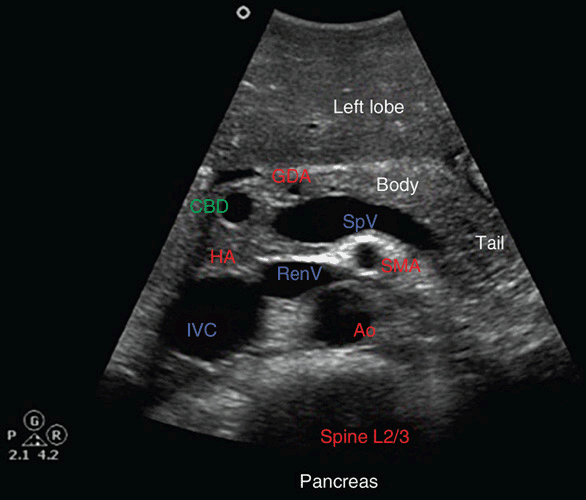

From radiologykey.com

Ultrasound of the Pancreas Radiology Key Ultrasound Vascular Quizlet In medical diagnostics, the us beam is reflected by clumps of moving red blood cells (rbcs) within blood vessels. What is the main focus of an insufficiency study?. They carry blood from the superficial veins to the deep veins, measure about 2mm diameter. Vascular ultrasound is a method in which a medical practitioner gets the chance to evaluate arteries or. Ultrasound Vascular Quizlet.